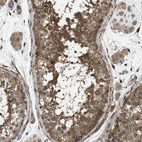

Immunohistochemical staining of human testis shows cytoplasmic positivity in cells in seminiferous ducts and Leydig cells.